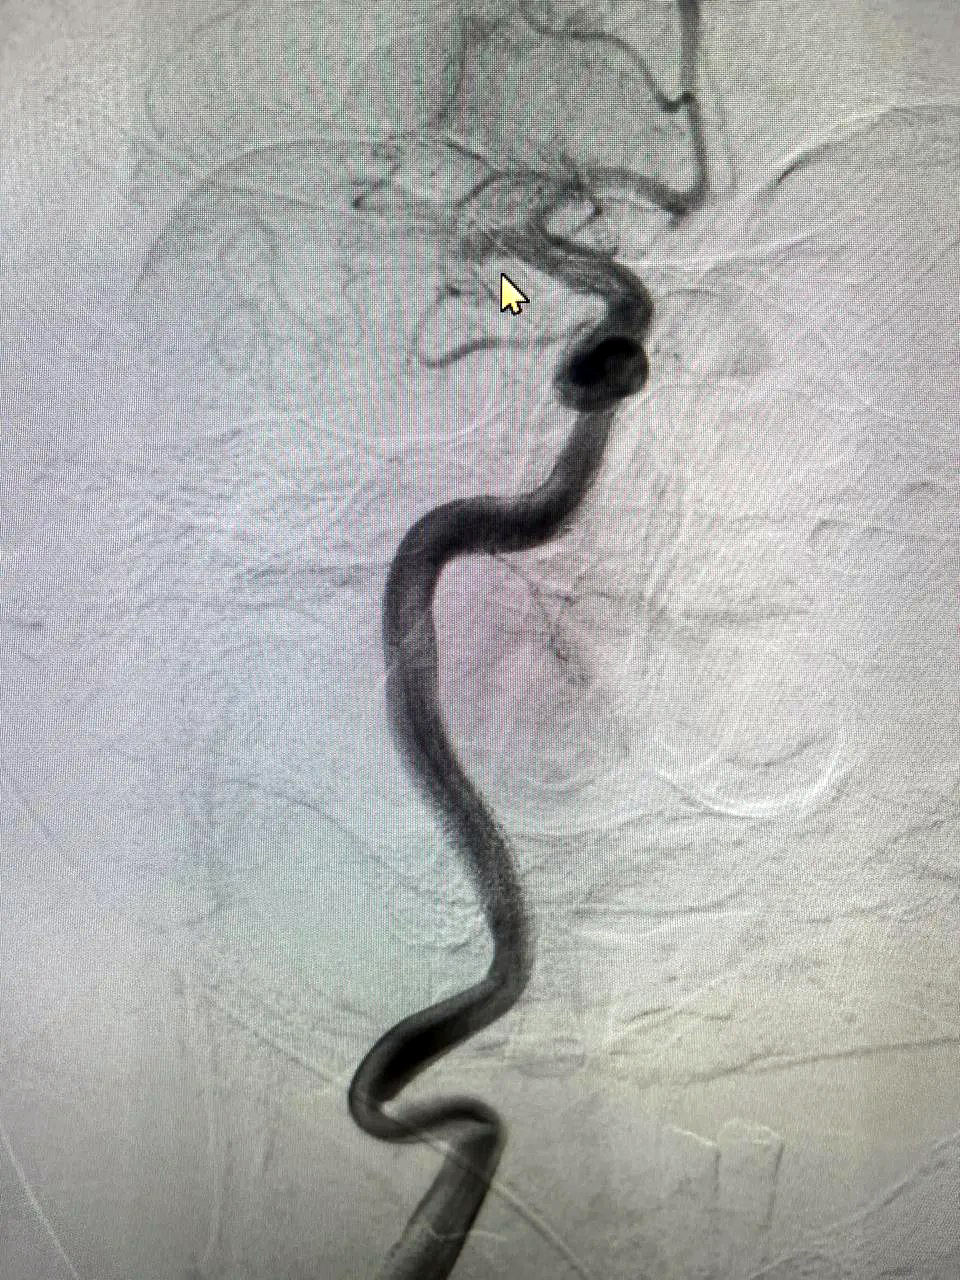

Как сообщает телеграм-канал БГКБ, процедура, называемая эндоваскулярной тромбэкстракцией, является мировым стандартом лечения ишемического инсульта. Её суть – в механическом извлечении сгустка крови, блокирующего артерию, через минимальный прокол. Это позволяет мгновенно восстановить кровоток и в разы увеличить шансы пациента на полное восстановление без тяжелой инвалидности.

В настоящее время прооперированный пациент находится под наблюдением в отделении реанимации, где получает необходимое лечение. На снимках, предоставленных больницей, запечатлены тромбы, ставшие причиной инсульта и успешно извлеченные из мозговых артерий.